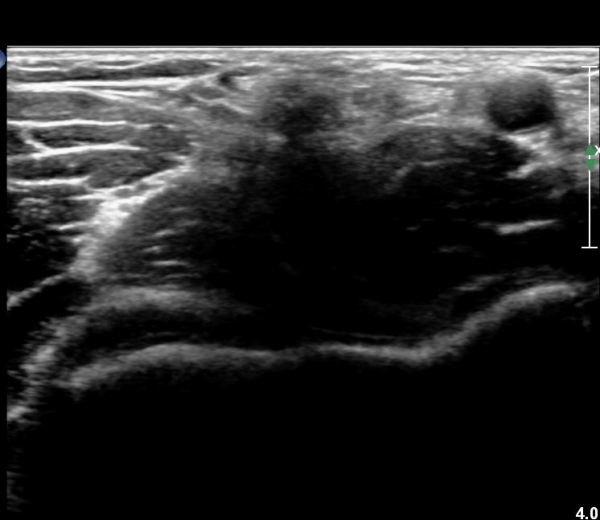

ÆÈ²ÞÄ¡ µÚÂÊ Á¾´Ü¸é°Ë»ç¿Í Ⱦ´Ü¸é°Ë»ç¿¡¼­ ÁֵοÍ(olecranon fossa)¿¡ ¼ö¾×Àú·ù°¡ °üÂûµÊ(»çÁø 1, 2)